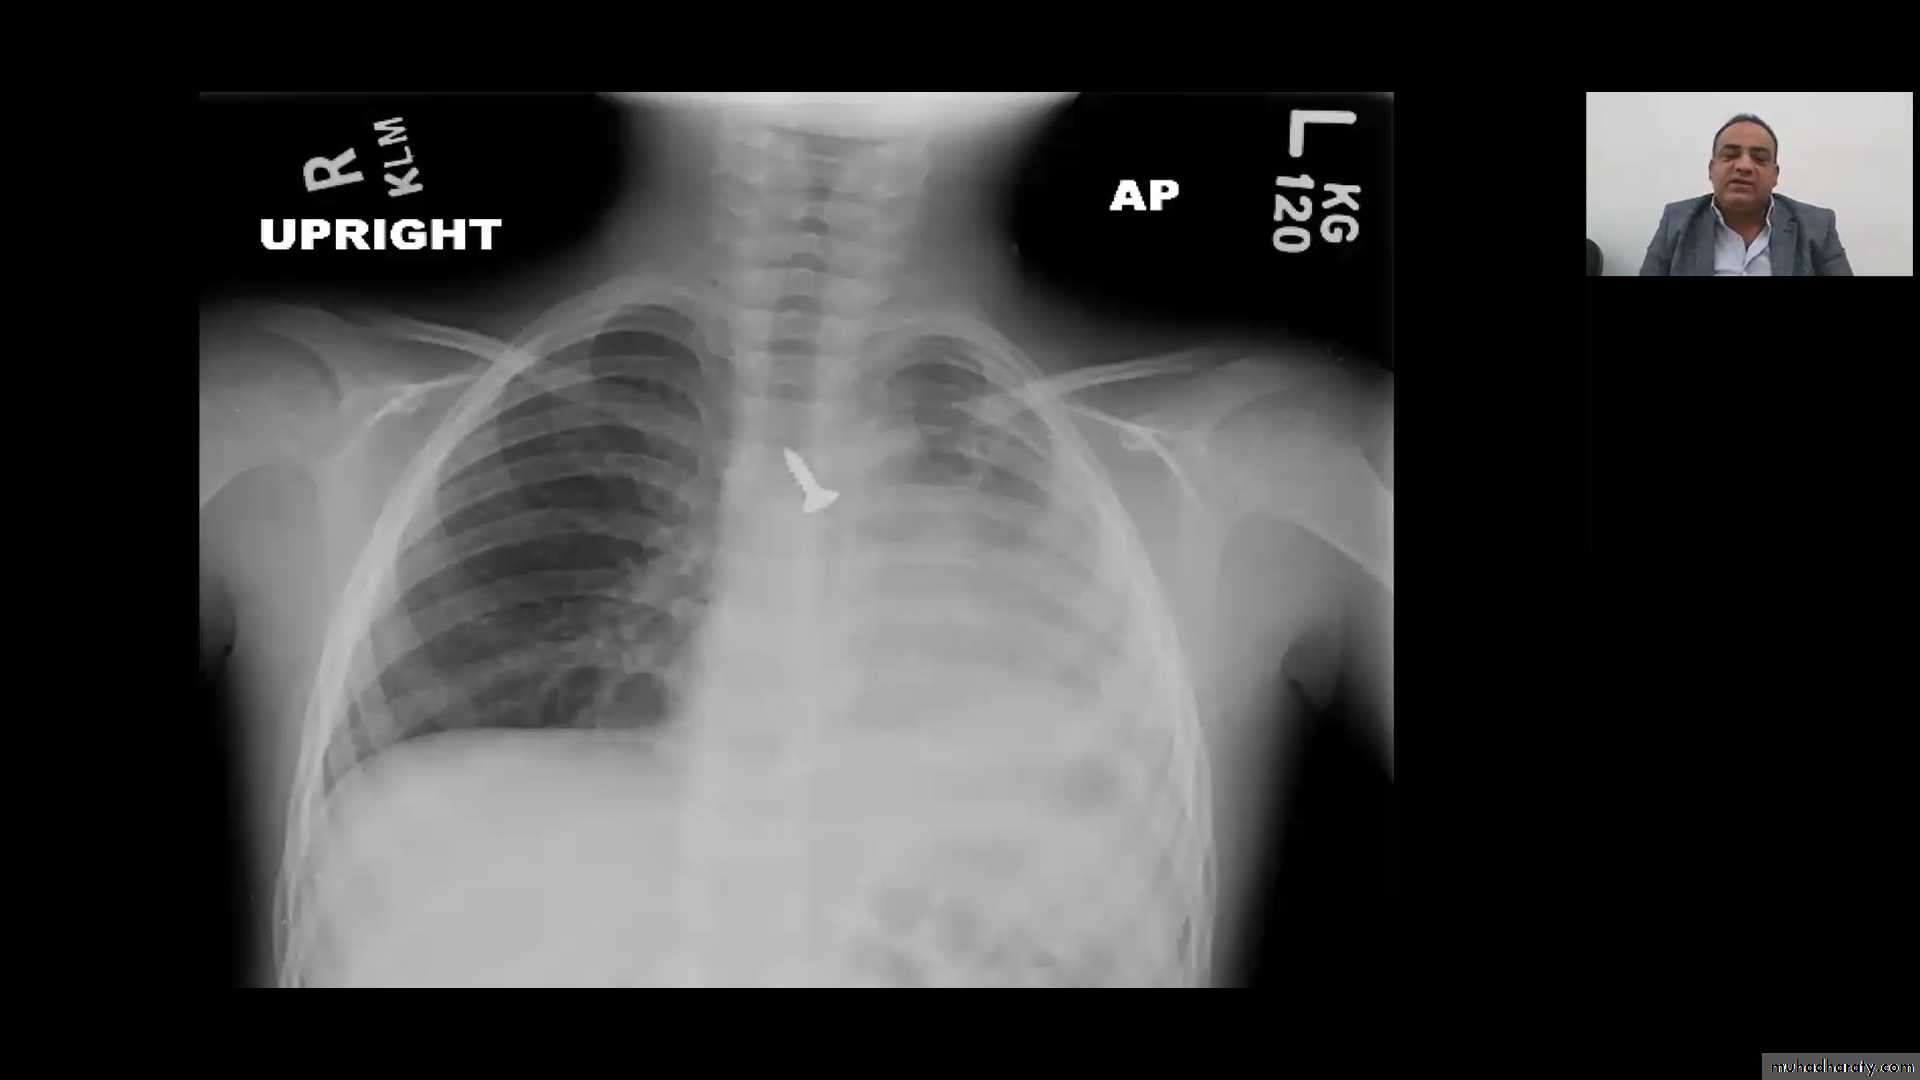

4 . X-ray of lateral neck give us thumb sign of swollen epiglottis .

X-ray in croup give us steeple sign due to narrowed subglottic space.